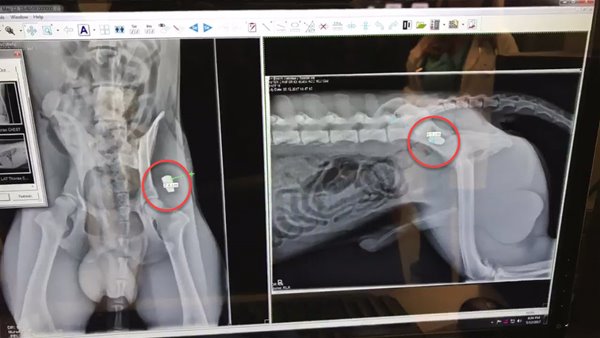

เจ้าตูบผู้กล้าหาญโดนกระสุนยิงเข้าที่บริเวณสะโพกด้านซ้าย มันถูกนำตัวส่งโรงพยาบาลสัตว์โดยทันที สัตวแพทย์เร่งผ่าตัดเอากระสุนออกให้แคสเปอร์ เคราะห์ดีอย่างมากที่กระสุนไม่ได้ทะลุเข้าไปถึงอวัยวะภายใน แคสเปอร์จึงไม่ได้รับบาดเจ็บหนักมากและรอดชีวิต